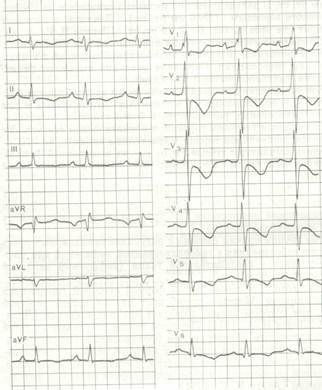

Дівчинка 11 міс. Cкарги батьків на швидку її втомлюваність при годуванні, раптове посилення ціанозу та задухи при плачі. Об¢єктивно: Стан середньої важкості, відставання в фізичному розвитку. В спокої – помірно виражений ціаноз шкірних покривів, слизові з фіолетовим відтінком, ціаноз посилюється при плачі дитини. Під час огляду на фоні неспокою значно посилився ціаноз, почастішало дихання, дитина стала вкрай неспокійною, на руках у матері з притиснутими до живота ніжками трохи заспокоїлась. Дихання 64 на хв, над легенями ясний перкуторний звук, жорстке дихання Пульс 150 за хв. Межі серця: розширені вправо. Над всією поверхнею грудної клітки вислуховується грубий систолічний шум із максимальною звучністю в 2-му міжребер'ї зліва від грудини, другий тон ослаблений над легеневою артерією. Загальний аналіз крові: Hb -200 г/л; еритроцити – 6,0 Т/л, КП – 0,95; нейтрофіли: паличкоядерні -5%, сегментоядерні -39%; еозинофіли-3%; лімфоцити-50%; моноцити - 3%; ШЗЕ - 4 мм/год. Рентгенологічне обстеження ОГК: див. рис.

Дівчинка 11 міс. Cкарги батьків на швидку її втомлюваність при годуванні, раптове посилення ціанозу та задухи при плачі. Об¢єктивно: Стан середньої важкості, відставання в фізичному розвитку. В спокої – помірно виражений ціаноз шкірних покривів, слизові з фіолетовим відтінком, ціаноз посилюється при плачі дитини. Під час огляду на фоні неспокою значно посилився ціаноз, почастішало дихання, дитина стала вкрай неспокійною, на руках у матері з притиснутими до живота ніжками трохи заспокоїлась. Дихання 64 на хв, над легенями ясний перкуторний звук, жорстке дихання Пульс 150 за хв. Межі серця: розширені вправо. Над всією поверхнею грудної клітки вислуховується грубий систолічний шум із максимальною звучністю в 2-му міжребер'ї зліва від грудини, другий тон ослаблений над легеневою артерією. Загальний аналіз крові: Hb -200 г/л; еритроцити – 6,0 Т/л, КП – 0,95; нейтрофіли: паличкоядерні -5%, сегментоядерні -39%; еозинофіли-3%; лімфоцити-50%; моноцити - 3%; ШЗЕ - 4 мм/год. Рентгенологічне обстеження ОГК: див. рис.

1. Який попередній діагноз? Яке ускладнення розвинулось у дитини? Опишіть патологічні зміни в аналізі крові, на ЕКГ, ЕхоКГ та на рентгенограмі.

Хлопчик 10 років. Скарги на підвищення температури тіла, в'ялість, дворазову блювоту, підвищену пітливість, появу набряків на нижніх кінцівках. Два тижні тому прооперований з приводу вродженої вади серця, в задовільному стані виписаний додому. Об¢єктивно: відставання в фізичному розвитку, блідість із ціанотичним відтінком шкірних покривів, пітливість, деформація пальців рук та ніг у вигляді "барабанних паличок" та нігтів у вигляді "годинникових скелець". Температура тіла 37,8°С, пульс 140 на хв, дихання 24 на хв, артеріальний тиск 80/40 мм рт.ст. На грудній клітці свіжий рубець після операції на серці. Межі серця різко розширені, права на 1,5 см назовні від парастернальпої лінії, ліва доходить до середньо-підпахвинної лінії. При натискуванні фонендоскопом вислуховується ніжний шум тертя перикарду на фоні послабленої гучності серцевих тонів. Над легенями провідні хрипи, більше в паравертебральній ділянці. Печінка на 4-5 см виступає з під реберної дуги. На нижніх кінцівках відмічається пастозність. ЕКГ,  ЕхоКГ та рентгенограма додається.

ЕхоКГ та рентгенограма додається.

В кардіологічне відділення поступив хлопчик 2,5 років. Скарги - напади задишки з ціанозом, дитина займає колінно-ліктьове положення. З дня народження вислуховувався систолічний шум, в зв’язку з чим дитина була направлена на консультацію до кардіолога.

При об’єктивному обстеженні стан дитини важкий. Відстає в фізичному розвитку. Відмічається ціаноз шкіри та слизових оболонок. Пальці рук та ніг мають форму „барабанних паличок”, нігті в вигляді „годинникових скелець”. ЧД- 46 за 1 хв.. Над легенями вислуховується везикулярне дихання. Деформація грудної клітки – правошлуночковий серцевий горб, виражена Гарісонова борозна. ЧСС – 140 за 1 хв., ритмічний, слабкого наповнення. Серцевий поштовх розлитий. Межі відносної серцевої тупості: верхня – 2 міжребір’я зліва, ліва – на рівні лівої середньоключичної лінії, права – по правій парастернальній лінії. Тоні серця ритмічні, другий тон ослаблений над легеневою артерією. Над усією ділянкою серця вислуховується грубий систолічний шум з епіцентром в 3 міжребір’ї зліва. Живіт м’який, печінка виступає на 4 см. з-під реберної дуги.. Ер. 8,9×1012/л., Нв - 186 г/, Лейк. -5,6×109/л. е - 5%, п - 2%, с - 29%, л - 57%, м - 7%, ШОЕ - 2 мм/год. Гематокрит – 0,65. Рентгенографія ОГК – кардіомегалія за рахунок гіпертрофії правого шлуночка, верхівка серця припіднята над діафрагмою, серцево-судинний пучок вузький, легеневий малюнок ослаблений, корені легень не визначаються.

2. Оцінити ЕхоКГ та ЕКГ.